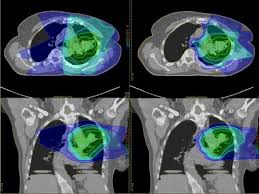

Is Proton Therapy Safer Than Traditional Radiation National Cancer Institute

Is Proton Therapy Safer Than Traditional Radiation National Cancer Institute from www.cancer.gov